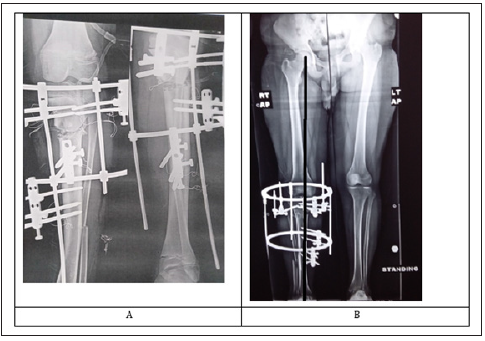

Postoperative antibiotics and analgesics were given. patients were discharged from the hospital on the second or third postoperative day. An immediate postoperative x ray of the knee and tibia was done (Figure 2). Weight bearing as tolerated was allowed and range of movement encouraged. Follow up at the clinic was at second week postoperative then monthly. A long standing X ray film (Figure 2) was done in the first visit to check correction. If there is overcorrection or under correction, the distractor was shortened or lengthened respectively. Patients were teached how to do pin site care daily using normal saline or alcohol. Full weight bearing was usually obtained in the first month.

Figure 2: A) Postoperative x ray of left knee and tibia. B) Long standing x ray film of another patient showing restoration of normal medial proximal tibia angle and limb alignment.